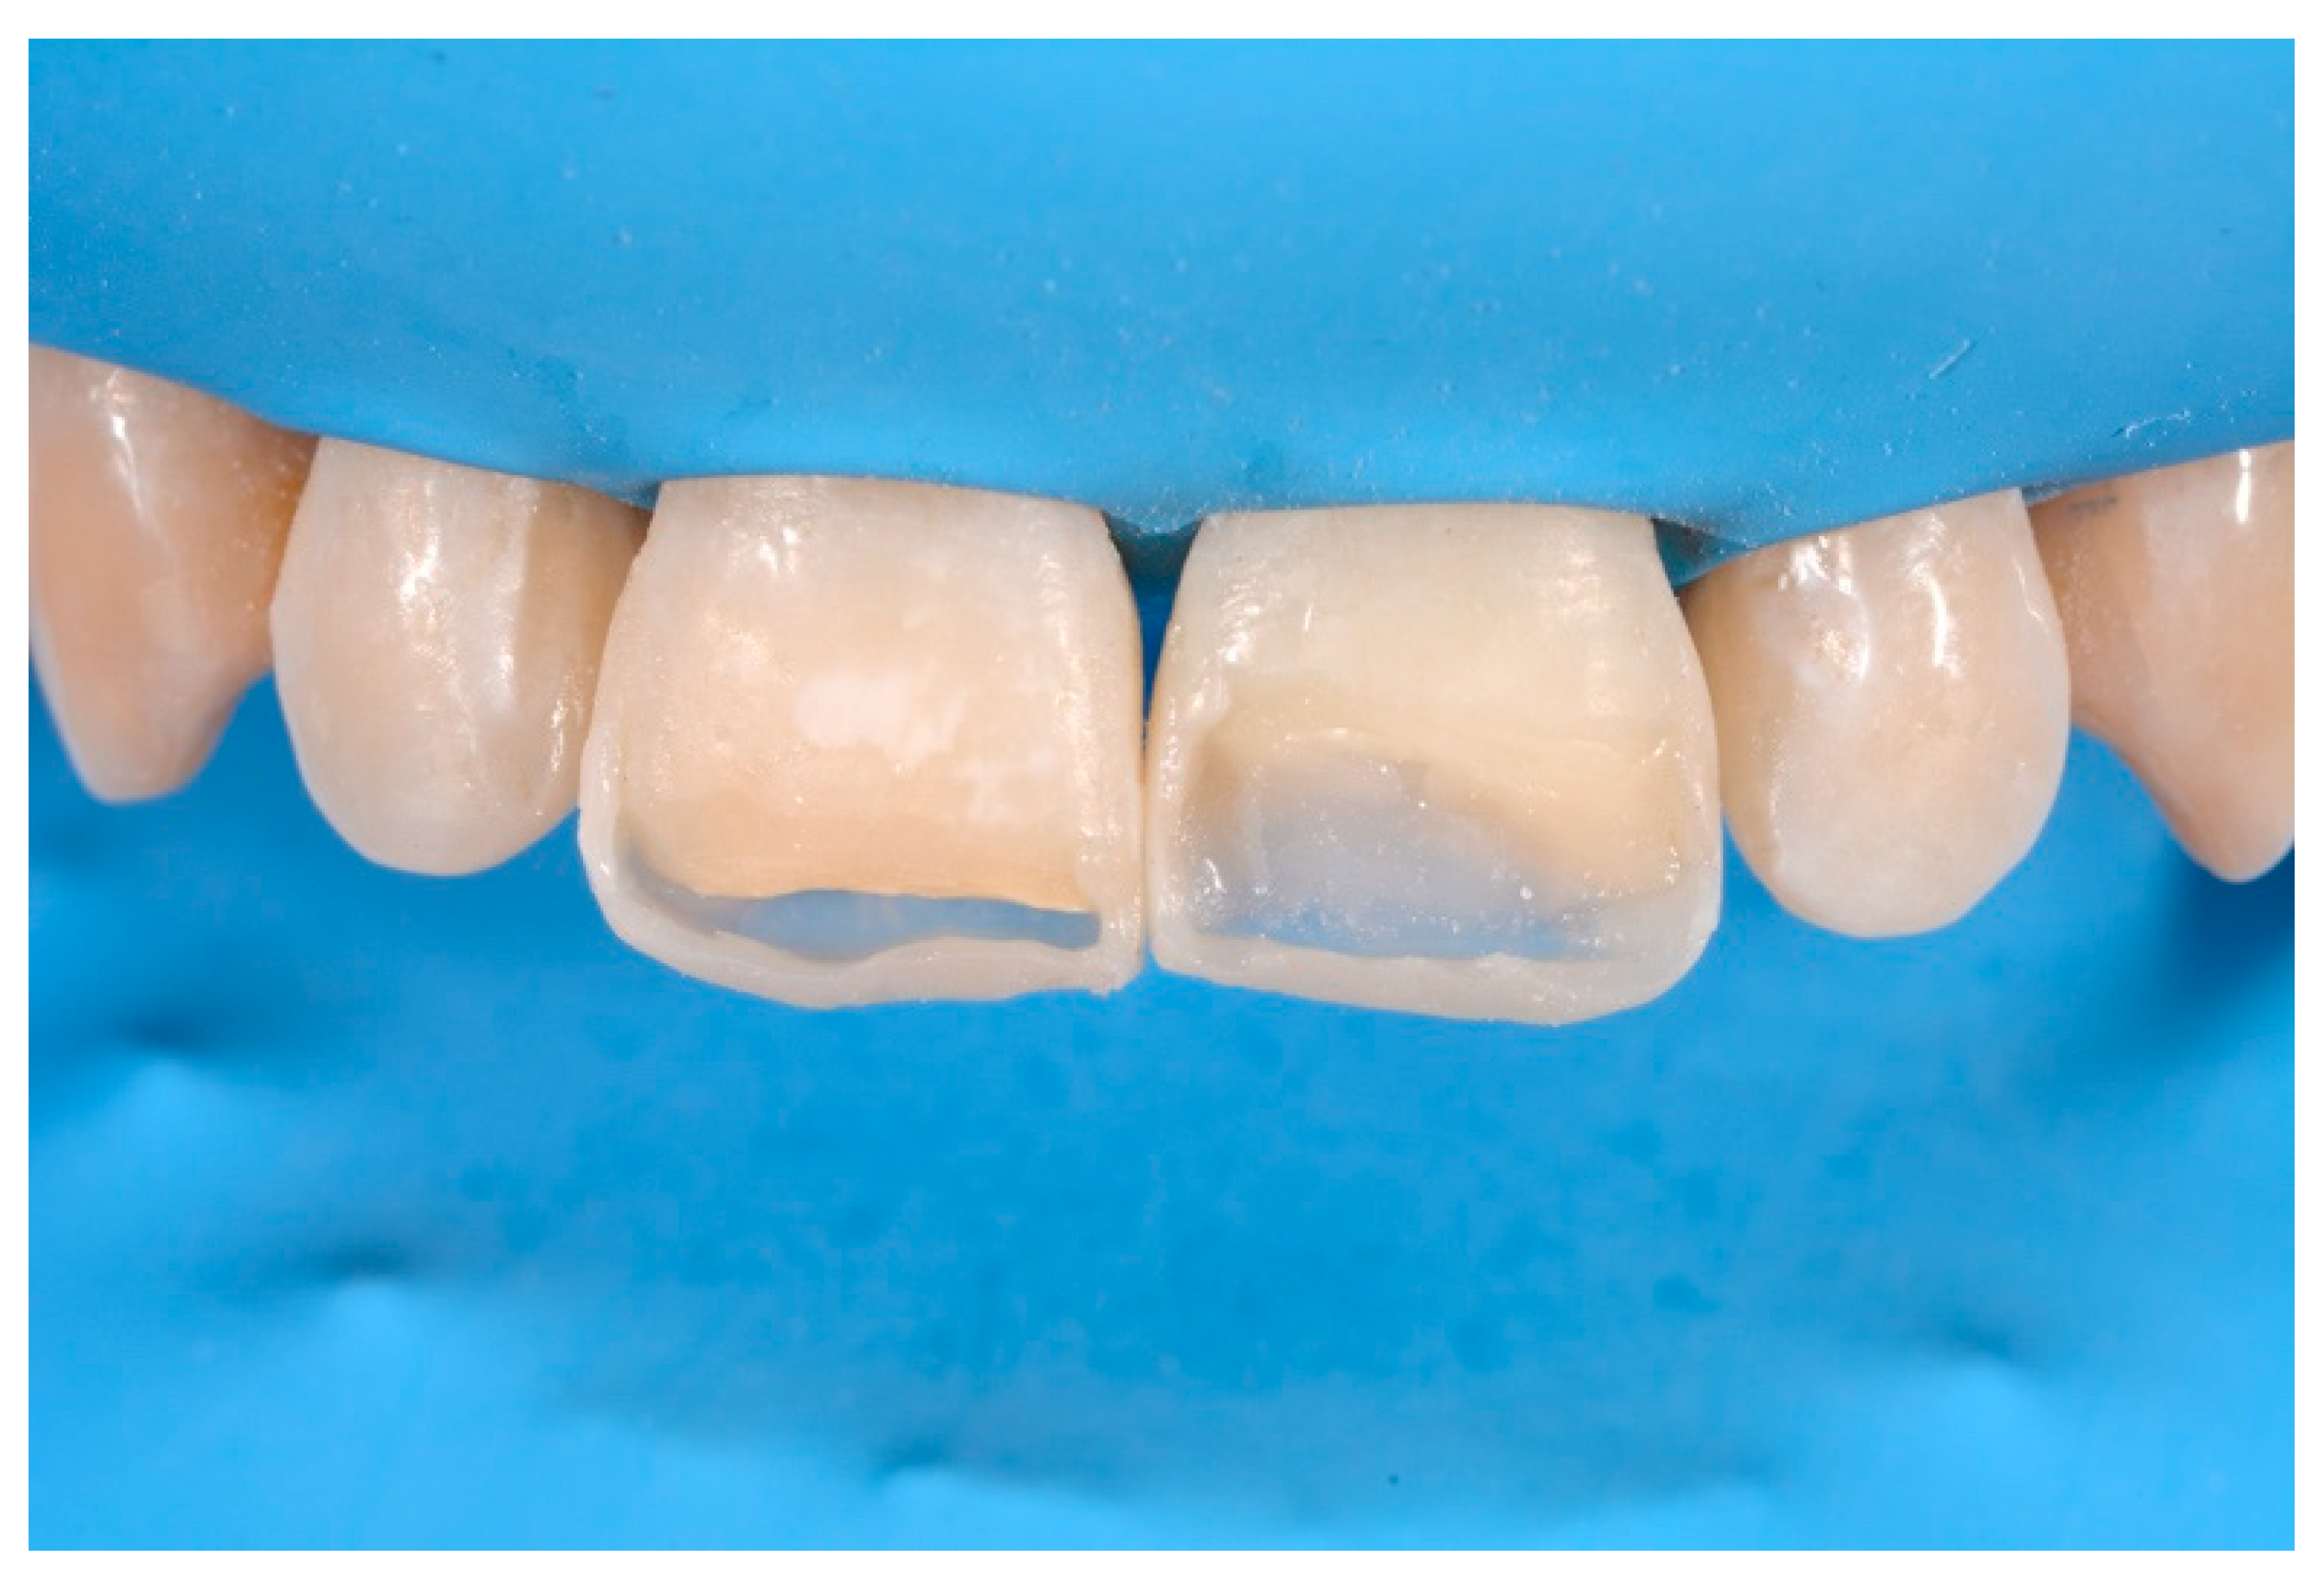

Figure 35.

The modified frames treated with silane coupling agent and adhesive, ready for layering of dentinal body. Reprinted from Restauri diretti nei settori anteriori, G. Paolone, S. Scolavino, © 2021, with permission from Quintessence Publishing Italy.

Once completed, the two frames (Clearfil Majesty ES-2, A1E, A2D, Kuraray Noritake Dental, Tokyo, Japan) showed internal and external excesses that were reduced using diamond burs and discs (Figure 33 and Figure 34) strictly following the procedure described in Section 2.1.2 of present article. Excesses were removed from the distal-incisal angle of #2.1 allowing therefore to obtain the desired translucency. After silane application and bonding procedure (Figure 35) as described in Section 2.1.2, restorations were completed (Figure 36 and Figure 37). They both show satisfactory clinical integration 1.5 years post-operative (Figure 38 and Figure 39).